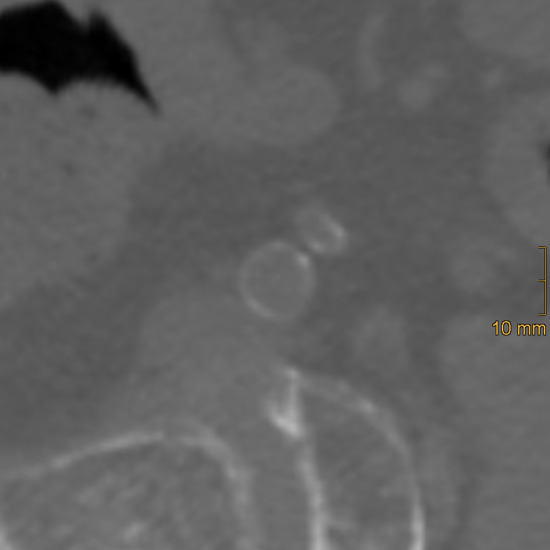

Background: Vascular calcification is a frequent consequence of ageing and is associated with an increased risk of cardiovascular disease. This study aimed to compare two rapid scoring systems for quantifying calcification of the distal abdominal aorta and iliac arteries and to investigate correlations with increasing age. Methods: Patients aged ≥65 years who sustained pelvic trauma between 2003 and 2023 and underwent computed tomography (CT) were included in this retrospective study. Patients were categorised into three age groups (65–74, 75–84, ≥85). The abdominal aorta calcification score (AACS) and the common, external, and total iliac artery calcification scores (CIACS, EIACS, TIACS) were assessed on cross-sectional images and classified into three severity grades (mild, moderate, severe). Results: A total of 224 patients (mean age 78.8 ± 8.5 years; 62% female) were included. Significant differences between age groups were identified for hypertension (p < 0.001), osteoporosis (p < 0.001), atrial fibrillation (p = 0.015), chronic heart failure (p = 0.004), chronic kidney disease (p < 0.001), neurocognitive disorders (p < 0.001), and anticoagulant therapy (p = 0.002). Calcification severity increased with age across all vascular territories (EIACS p = 0.006; others p < 0.001). In multivariable linear regression, age remained the strongest adjusted predictor of calcification across all vascular regions (β = 0.323–0.376, all p < 0.001). Significant positive correlations were found between aortic and iliac calcifications (all p < 0.001), strongest between AACS and CIACS (ρ = 0.78, CI 0.719–0.835) and TIACS (ρ = 0.745, CI 0.676–0.807). Corresponding categorical associations were most pronounced between AACS and CIACS. Conclusions: The evaluated calcification scores were strongly correlated and demonstrated clear age-dependent trends. Given their simplicity and applicability to routine CT imaging, these methods may provide practical tools for assessing vascular ageing. Full article